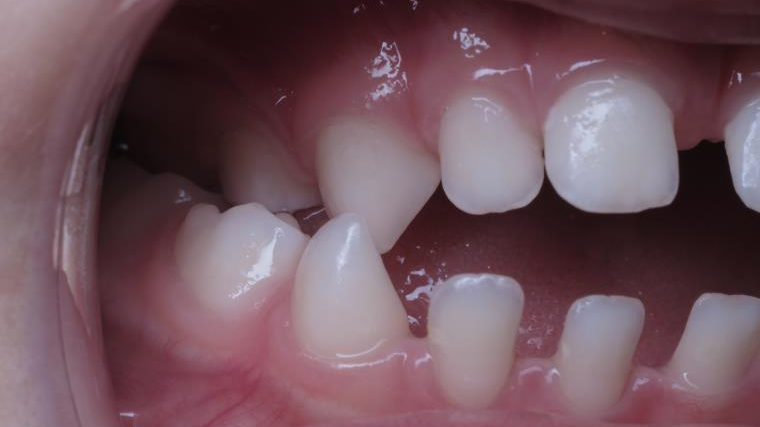

18 béance inversé droit 4 ans

inversion des dents postérieur et espace entre l'arcade du haut et du bas (béance)